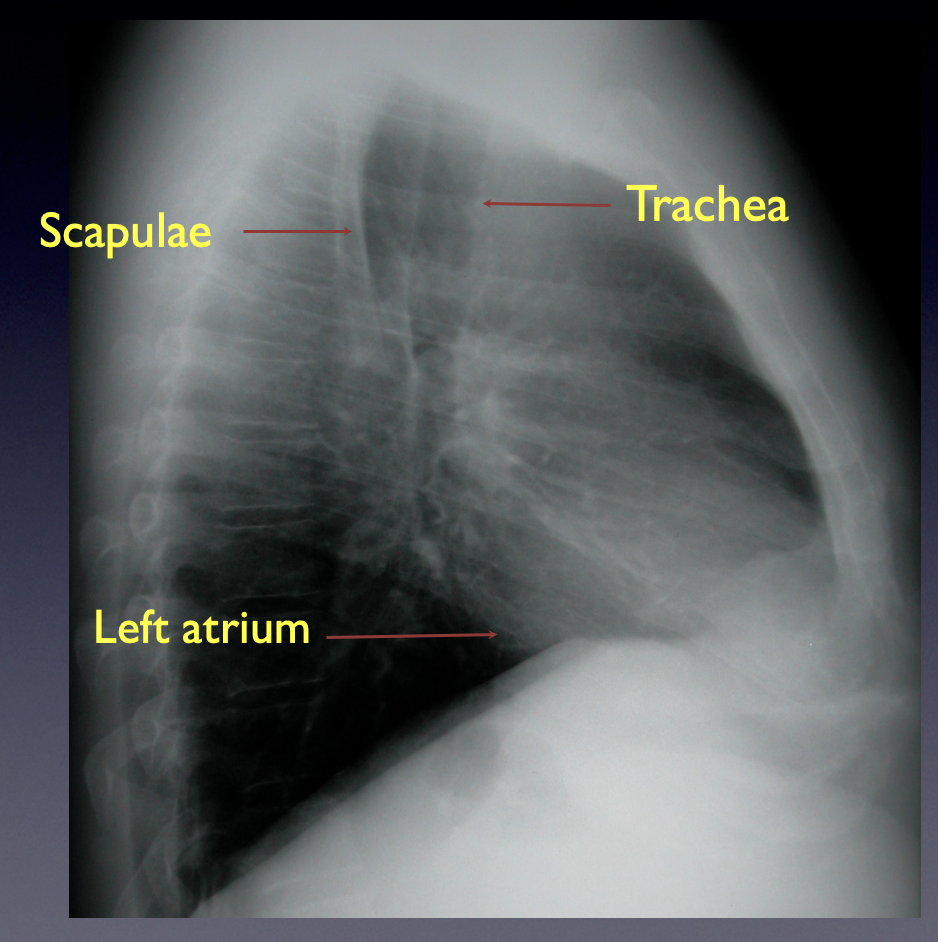

13

Q

Go

A

The retrosternal and retrocardiac spaces should be dark on a lateral CXR.

-If they are not, disease is present

Normal CXR